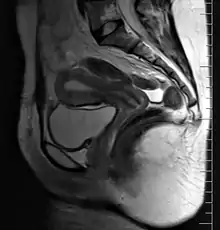

矢狀面